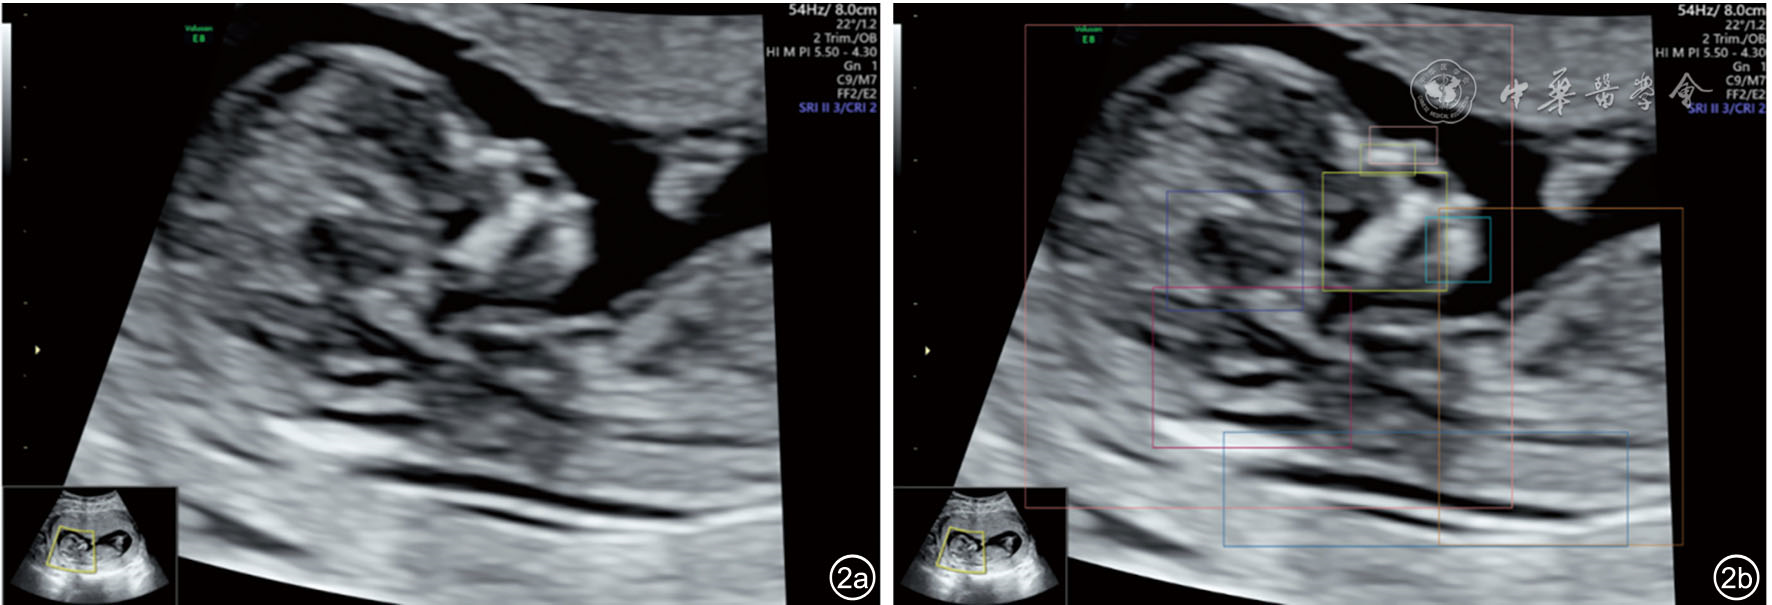

图1 产前超声人工智能智慧云平台对胎儿头臀长切面质量控制超声图像。质量控制结果包括检测结构显示情况(鼻骨、鼻尖和鼻前皮肤、上颌骨、下颌骨、间脑、菱脑、生殖器、侧脑室、头、胸、腹、臀)和总体评价,总体评价包括切面名称、切面质量(标准)、切面评分(94分)、结构置信系数评价(鼻骨:0.53,鼻尖和鼻前皮肤:0.68,上颌骨:0.86,下颌骨:0.46,间脑:0.89,菱脑:0.83,生殖器:0.80,侧脑室:0.69,头:0.89,胸:0.80,腹:0.81,臀:0.78)及不足原因。图a为原图,图b为质量控制标注图 |